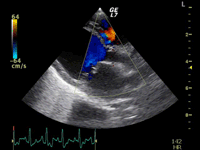

A

B

C

A:超音波カラードップラーでの僧帽弁逆流速度の測定

B:E波とA波の測定

C:僧帽弁逆流の動画(大きく表示させたい場合は、ココをクリックして下さい。)